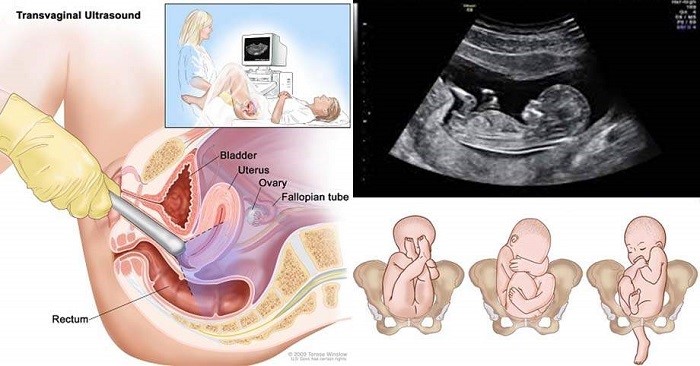

Như đã nói ở trên để theo dõi quá trình phát triển của thai nhi thì bác sĩ sẽ tiến hành 2 kĩ thuật, đó là siêu âm qua ngả âm đạo và siêu âm qua thành bụng.

Đối với siêu âm qua ngả âm đạo thì bác sĩ sẽ sử dụng một đầu dò thoa gel bôi trơn, co vào âm đạo và phát sóng âm để thu được hình ảnh hoàn chỉnh của bé. Phương pháp này rất an toàn, không gây ảnh hưởng cho sức khỏe hay bất kì đau đớn nào nhưng sẽ khiến bạn khá lúng túng. Tuy nhiên khi thai dưới 10 tuần tuổi, kích thước còn có bé nên buộc phải sử dụng phương pháp này mới nhìn thấy hình ảnh của bé qua màn hình.

Trong khi đó, khi bé đã trên 1 tuần tuổi thì có thể thay thế bằng phương pháp siêu âm qua thành bụng. Bác sĩ sẽ sử dụng dụng cụ siêu âm, bôi gel lên đó và sẽ rà khắp mặt bụng, trên màn hình sẽ hiện lên hình ảnh của thai nhi. Phương pháp này đã có mặt trên khắp các phòng khám, bệnh viện trên cả nước và được sử dụng thường xuyên trong y học.